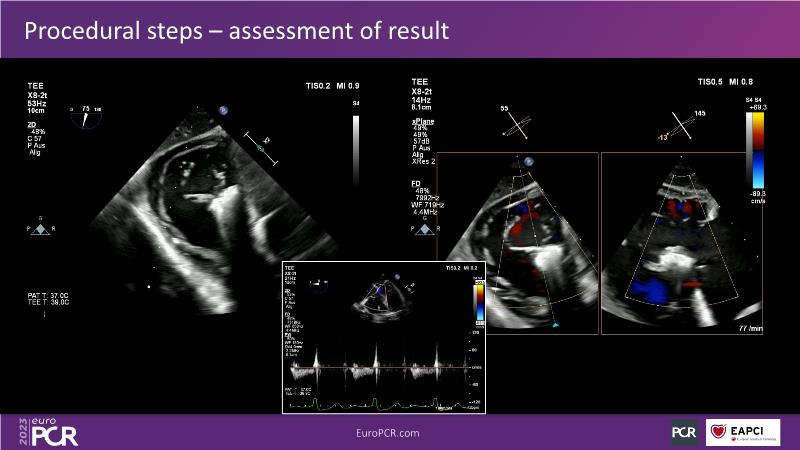

Tailoring tricuspid regurgitation patient treatment with the PASCAL Precision system

Watch this session to discuss exciting cases of tricuspid regurgitation, learn about the proposed new integrated classification for tricuspid regurgitation and enjoy a live presentation of the PASCAL Precision Repair System using a beating heart simulator, among others!

- To discuss the different tricuspid regurgitation phenotypes that can be treated with the PASCAL Precision repair system

- To participate in a case-based discussion using the PASCAL Precision repair system for the treatment of tricuspid regurgitation